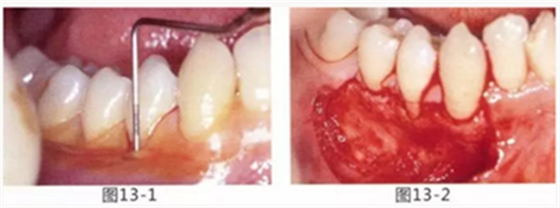

由于口腔前庭較淺且沒(méi)有附著齦,使菌斑容易滯留且刷牙困難的病例

圖13-1 使用碘溶液進(jìn)行染色,頰側(cè)基本看不到角化牙齦,且無(wú)口腔前庭的狀態(tài)。

圖13-2 為了擴(kuò)張口腔前庭,獲取附著齦而進(jìn)行了游離齦移植術(shù)。受皮床一定不能發(fā)生移動(dòng),盡可能使厚度均等。

圖13-3 手術(shù)剛結(jié)束的狀態(tài)。通過(guò)骨膜縫合的褥式縫合將移植片固定,使其無(wú)法移動(dòng)。

圖13-4 手術(shù)完成2年后的狀態(tài)??谇磺巴サ玫綌U(kuò)張,即使正在進(jìn)行正畸治療,也沒(méi)有妨礙到清潔。